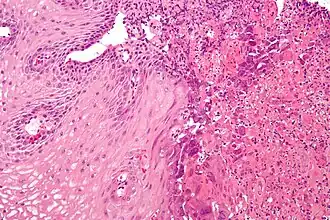

El término general esofagitis designa cualquier inflamación, irritación o hinchazón del esófago.[1] La esofagitis puede ser asintomática o puede causar dolor ardiente epigástrico o subesternal, especialmente al acostarse o hacer un esfuerzo, y puede dificultar la deglución (disfagia). La causa más común de esofagitis es el flujo inverso de ácido desde el estómago hacia la parte inferior del esófago: enfermedad por reflujo gastroesofágico (enfermedad por reflujo gastroesofágico o ERGE).[2]

El daño anatómico parece guardar mejor relación con la exposición prolongada del esófago al material refluido, la mayoría de las personas experimentan síntomas de reflujo sin daño de la mucosa esofágica, debido a la duración corta del reflujo.

Las consecuencias de la esofagitis por reflujo intenso son:

- hemorragia

- ulceración

- desarrollo de esófago de Barrett